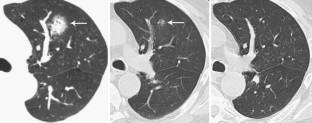

Fig. 4